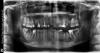

Мохов Опубликовано 19 июля, 2011 Поделиться Опубликовано 19 июля, 2011 Здравствуйте!Посоветуйте, пожалуйста, примерный план лечения в моём случае. Всё что нужно сделать, чтобы было хорошо и на что можно надеяться Что исправлять, что пломбировать, куда импланты, куда коронки и какие. Ссылка на комментарий

Salma Опубликовано 19 июля, 2011 Поделиться Опубликовано 19 июля, 2011 Здравствуйте!Посоветуйте, пожалуйста, примерный план лечения в моём случае. Всё что нужно сделать, чтобы было хорошо и на что можно надеяться Что исправлять, что пломбировать, куда импланты, куда коронки и какие.удалять зубы 15,26,36, зубы 37,46и47 тоже име5ют шанс быть удаленнымиперелечивать центральные верхние резцы,12,25лечить 13,23,38,35,41,48на депульпированные зубы с большими пломбами и которые разрушены,если успешно полечите, перелечите вкладки и коронкина место удаленных имплантыкак то так... Ссылка на комментарий